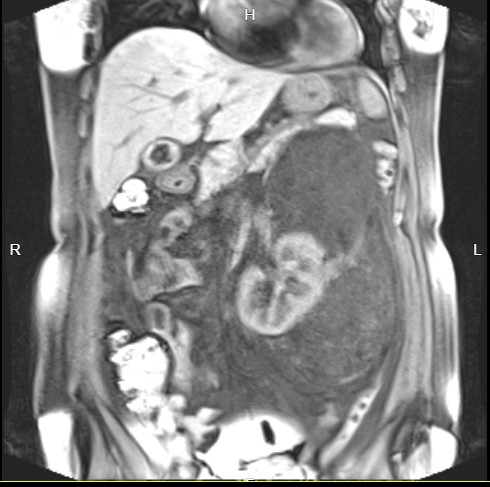

图片发自160App

|CT|准确性高于B超,对肿瘤的定位、大小、范围、与邻近脏器的关系显示更为直观和清楚,增强扫描可以显示肿瘤和周围血管的关系,肿瘤内出现脂肪密度为其特征|发现率89%|

|磁共振|在发现肿瘤范围及其与周围组织和血管的关系时,优于CT||